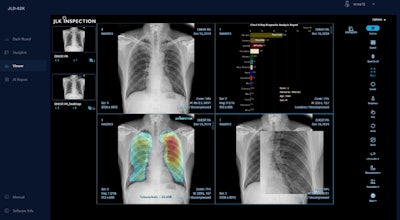

JLK's AI-based lung disease analysis algorithm JLD-02K allows doctors to make tuberculosis diagnoses more effectively. The software aims to address the problem of low radiologist capacity while also reducing screening expenses.

JLD-OK is an AI-enabled lung disease analysis software. Image courtesy of JLK Inspection.

JLD-02K doesn't have to run on a high-end workstation and can instead be used on mini personal computers or laptops, according to the company.